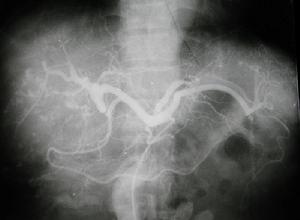

3.肝血管造影 肝動脈造影能為該病的診斷提供有價值的資料發現異常血管形態腫瘤周邊部持續染色和中央放射狀透光區都高度提示肝血管肉瘤。